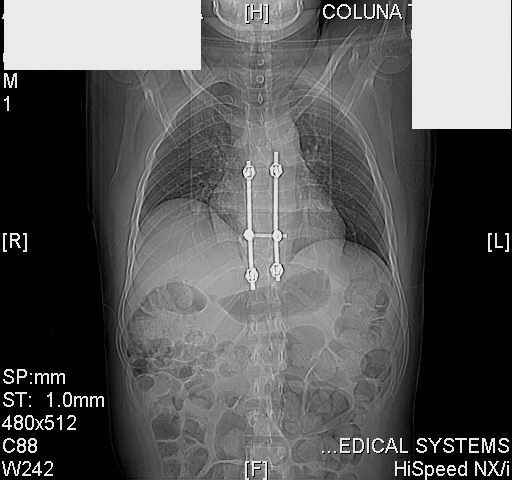

Коллеги,Шуруп в аорте? Как снимать конструкцию? Нужен ли контроль аорты? Читайте ниже.С уважением, д-р Архипов

dear all (George?) Got a note this morning requesting an opinion about a patient 25 yrs froma remote area of the country who received this "excellent" stabilization of a fracturedthoracic spine over a year ago.The original neurosurgeon liberated the patient for fullactivities and rehab etc.The rehab doc wants to know what to do. Looks to me like the patientwas screwed pretty good! any offers?

Tom, Harrington rods from a medical museum, with industrial strength screws from a boatbuilder. What are the current symptoms?

Interesting case. Findings on CT: all four pedicle screws have been placed improperly inthat they miss the vertebral bodies. In addition, the screws on the left side are impingingon the decending thoracic aorta. What I do NOT know is the nature of the original injury, orwhether or not that injury has resolved. I would recommend removal of the hardware. I don'tthink it's a good idea to leave those screws where they are. If the original fracture ishealed, nothing else needs to be done.

dear Mark, all the details are not yet available but the patient is coming to see us foradvice. We probably will see him in the early new year. i thought that the 4th picture showedthe screw to enter the aorta? He is a victim of a motor vehicle crash and thoracic vertebralfracture which appears healed. He was posteriorly decompressed and this device inserted. asyou say there isno evidenece that any of the fixation enters the bodies via the pediclesistead they have passed thru and their end are no where near where they ought to be. If I amcorrect (I would prefer not to be) the aortic intima has been breached by the screw. When thetime comes to take the screw out I thought we should have control of the aorta.What do you think?